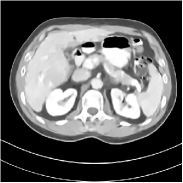

Fig. 3 illustrates the image evolution over SUPER layers (i.e., with evolving network weights in the iterative reconstruction process) for one test case, when using SUPER-WRN-ULTRA. It is apparent that in the early SUPER layers, the proposed SUPER-WRN-ULTRA method mainly removes noise and artifacts, while later SUPER layers mainly reconstruct details such as the bone structures shown in the zoom-in box. A similar behaviour is observed with FBPConvNet-based SUPER methods, which are shown in the supplement (Figs. 13 and 14).

Refer to caption Refer to caption Layer 1RMSE =27.44 HURefer to caption Refer to caption Layer 5RMSE = 26.03 HU

Refer to caption Refer to caption Layer 11RMSE = 25.91HURefer to caption Refer to caption Reference

Figure 3: Image evolution over SUPER layers using the SUPER-WRN-ULTRA method. RMSE values are also indicated.